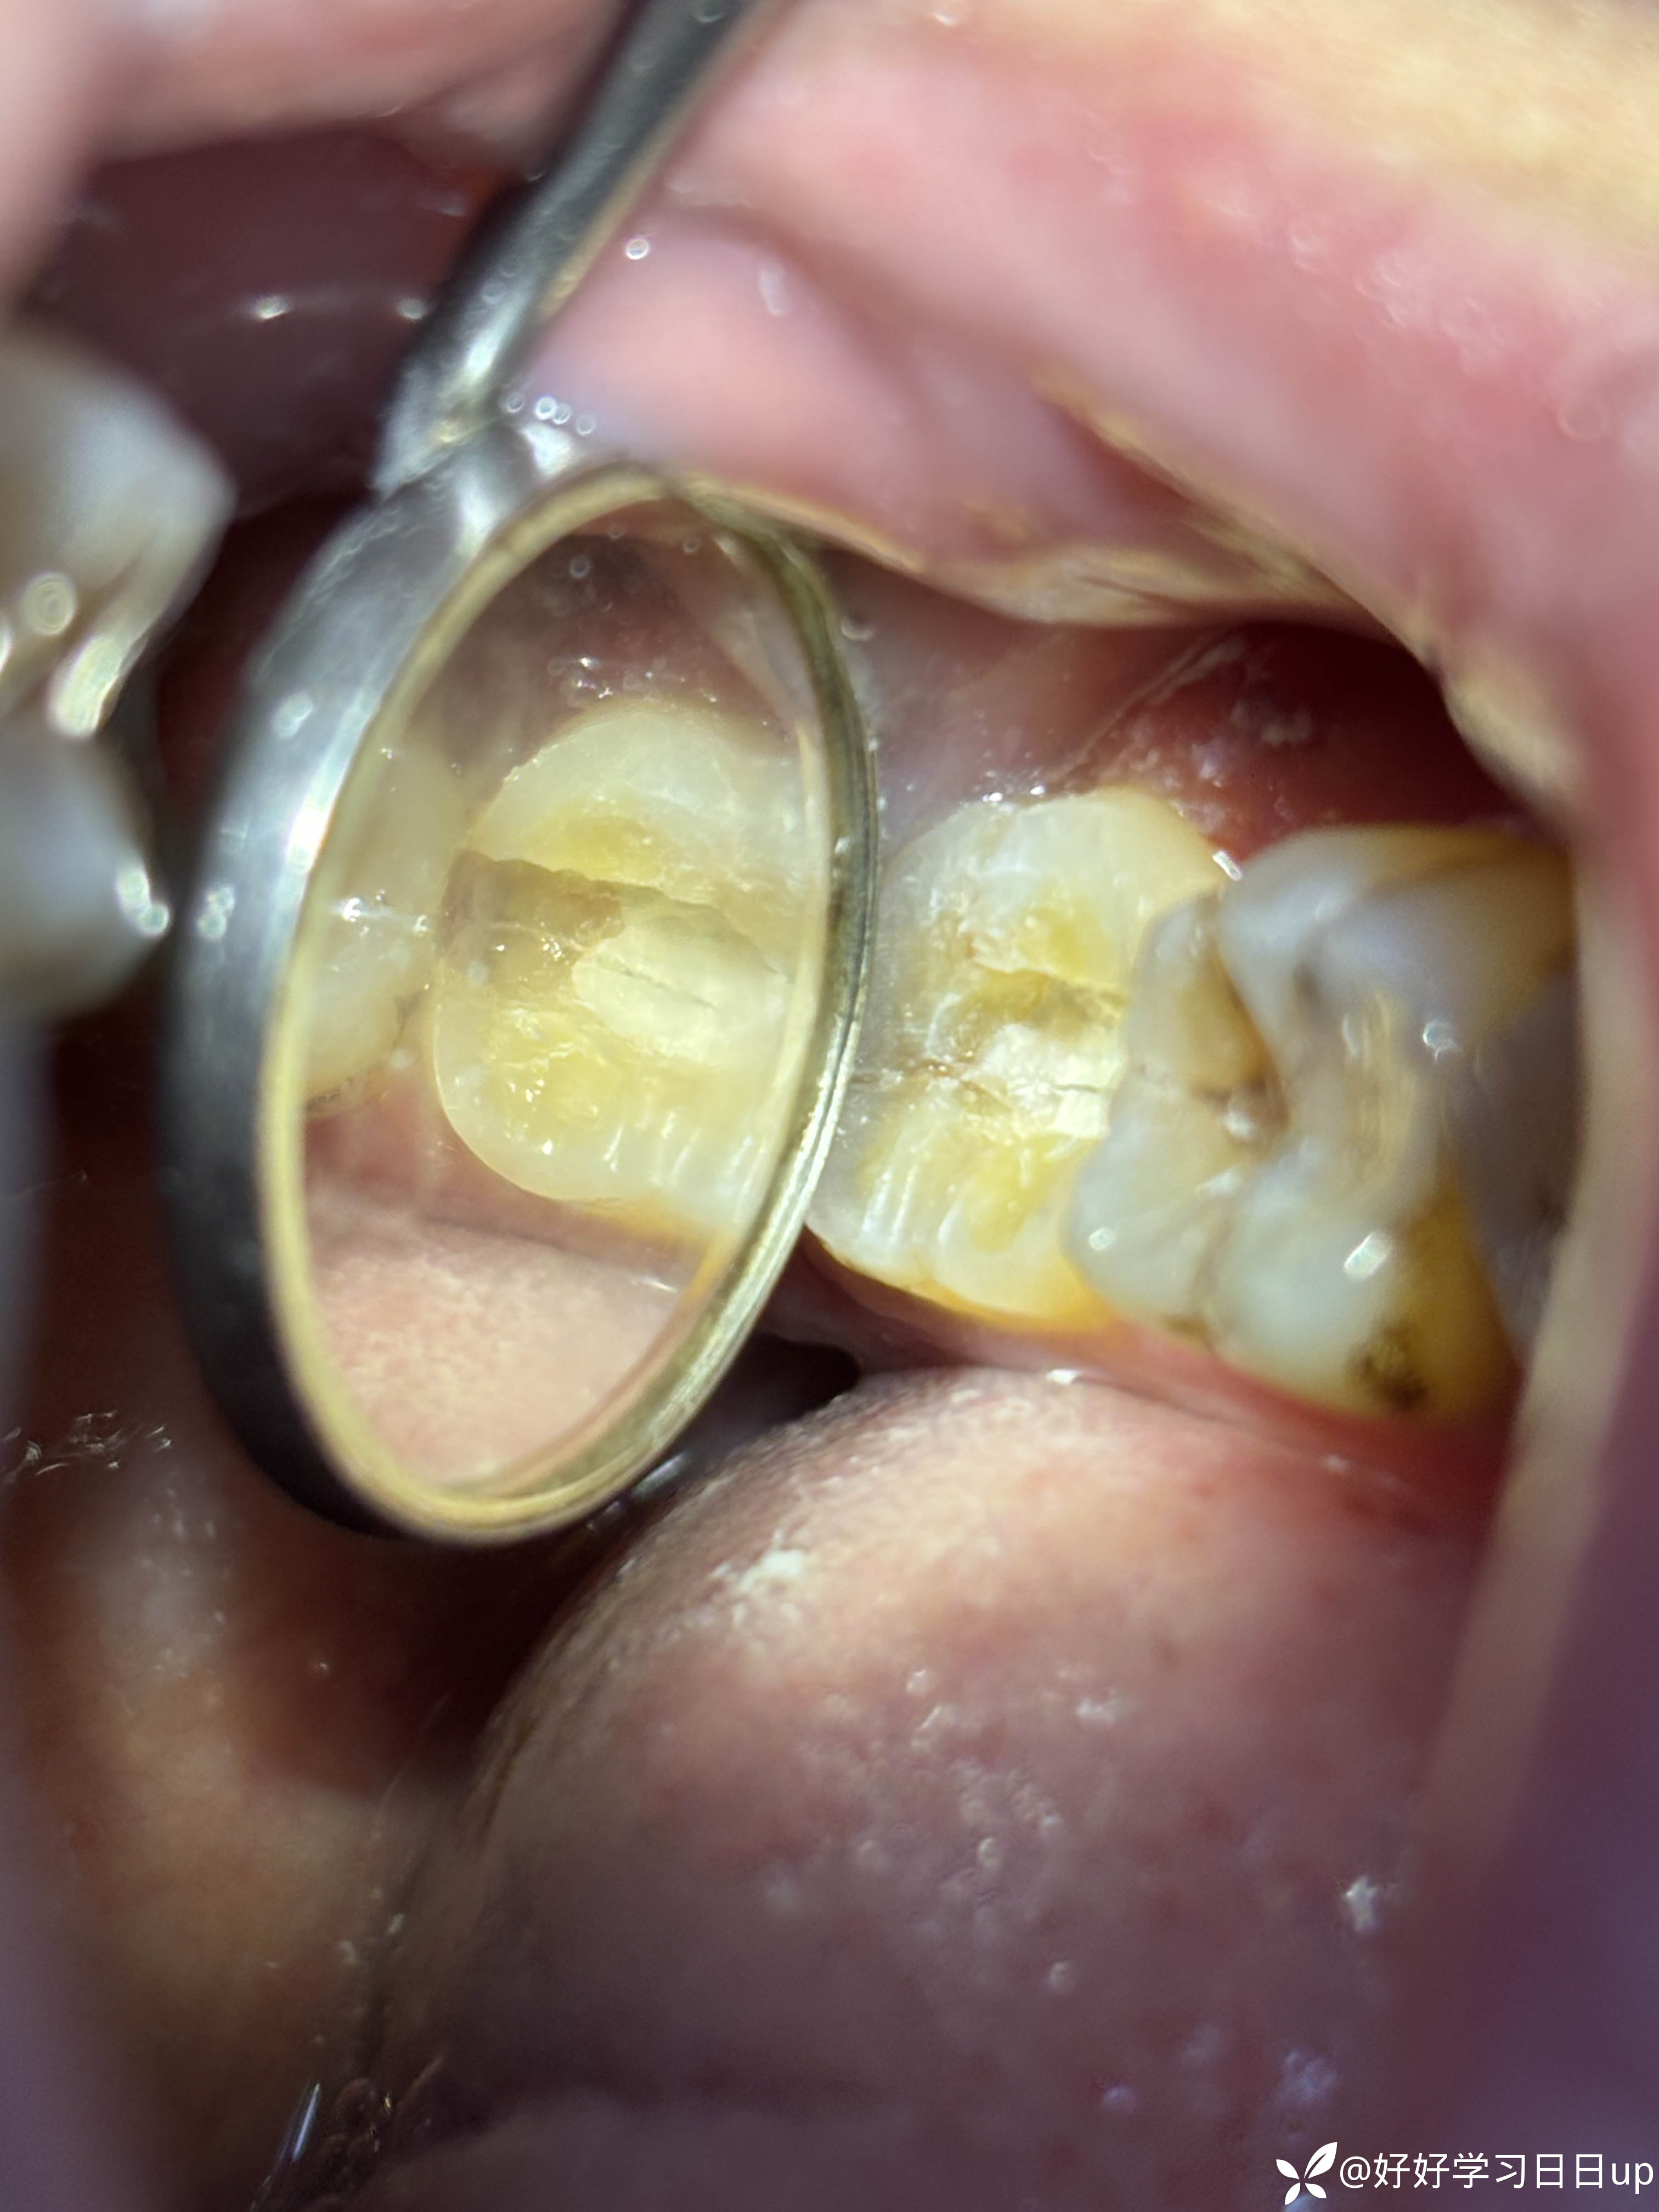

今天来了说肿了补的位置牙线用的过程中掉了一块,口内看可能是牙周脓肿,于是拍了一张根尖片,感觉不是根管引起的瘘管,引流脓液,洁治后,发现近中缺损部位疑似隐裂,拆除充填体发现隐裂贯穿近远中但是裂的位置卡不进探针,再次向下打磨隐裂部位,本来想完全去除隐裂,但没想到裂的还是比较深害怕抗力越来越差,跟患者说可能需要拔除,或者降低咬合后续观察,患者选择降低

我当时的想法是做一个树脂嵌体,但是想想好像也没作用,直接流体填起来降低到咬不到,颌面流体颊舌向做了一道杠想着给牙一个像中心的力量(瞎搞的也是没招了),老师们遇见这种是直接建议拔除还是有其他方法?是隐裂引起的脓包吗?